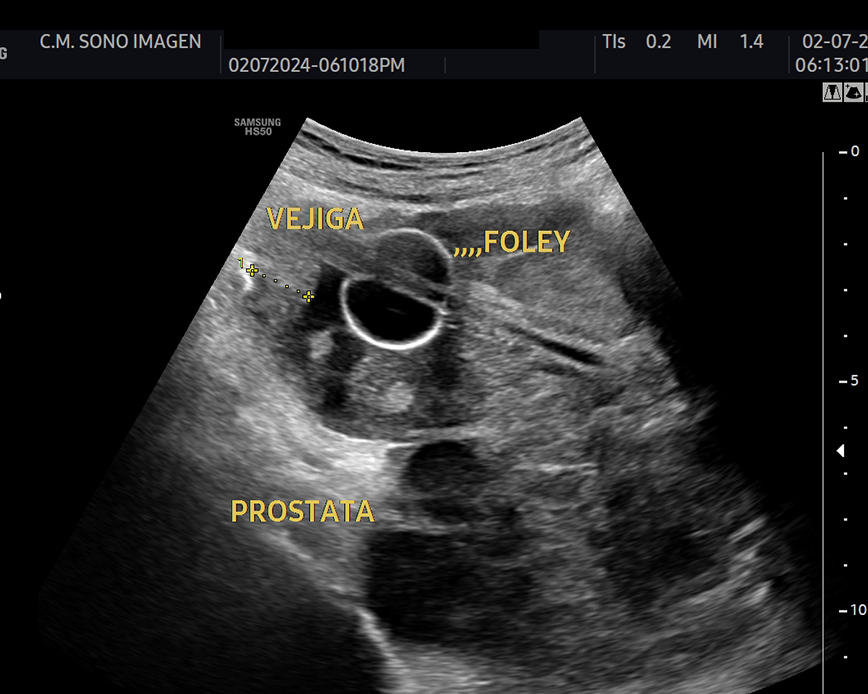

Ecografía Prostática

- hiperplasia prostática benigna(HPB)

- dificultad para orinar o retención urinaria

- control postquirúrgico o postratamiento